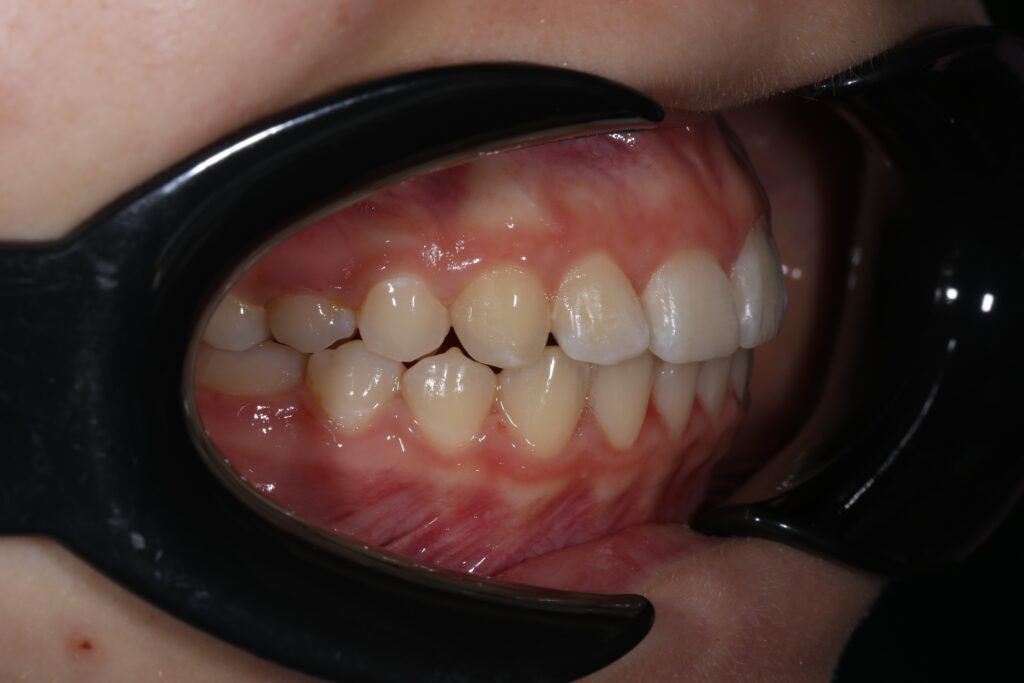

Ситуация до лечения

Жалобы: Пациентка обратилась с жалобами на неровное положение передних зубов.

Диагноз: дистальный прикус, сужение верхнего и нижнего зубных рядов, скученность фронтальной группы зубов на верхней и нижней челюсти.

пациент до лечения брекетами